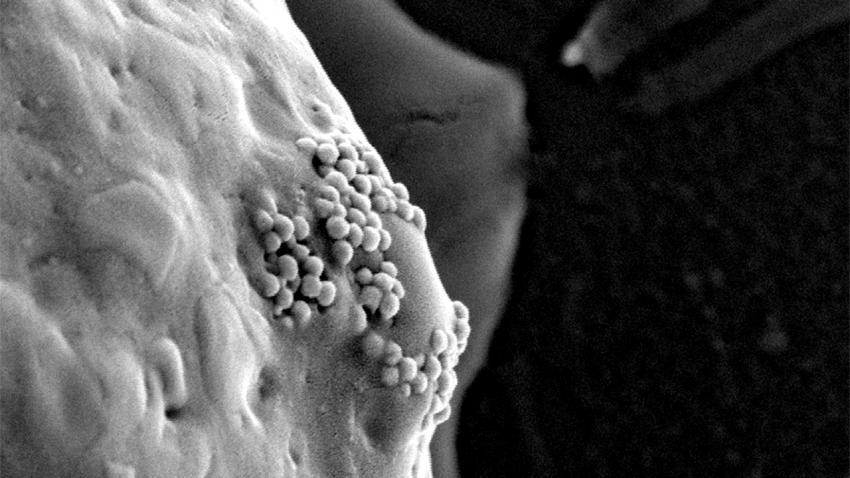

Thông thường, các khối u rắn thường có các mạch máu rò rỉ. Do đó, khi các hạt nano vàng được tiêm vào máu, chúng sẽ đi qua các lỗ mạch bị mở này và vào bên trong khối u. Khi các tế bào ung thư phát triển chúng sẽ bao phủ các hạt nano vàng này.

Tuy nhiên, sau khi đã vào được bên trong, các hạt nano này sẽ giống như những chú ngựa Trojan. Khi các nhà khoa học đốt nóng các hạt nano vàng đã được tiêm vào máu, các hạt này sẽ nóng lên đồng thời tiêu diệt các tế bào ung thư.

Tuy nhiên, phương pháp này còn một thay đổi quan trọng: Do nhiệt độ của các cụm nguyên tử nano vàng nóng lên nó cũng đốt nóng xung quanh, làm bốc hơi các phân tử nước lân cận, tạo nên các bong bóng nhỏ xíu nhanh chóng phình to rồi nổ tung xé các tế bào ung thư. Các cụm hạt nano tạo ra các bong bóng nano trong tế bào ung thư và tiêu diệt chúng mà không ảnh hưởng tới các tế bào lành.